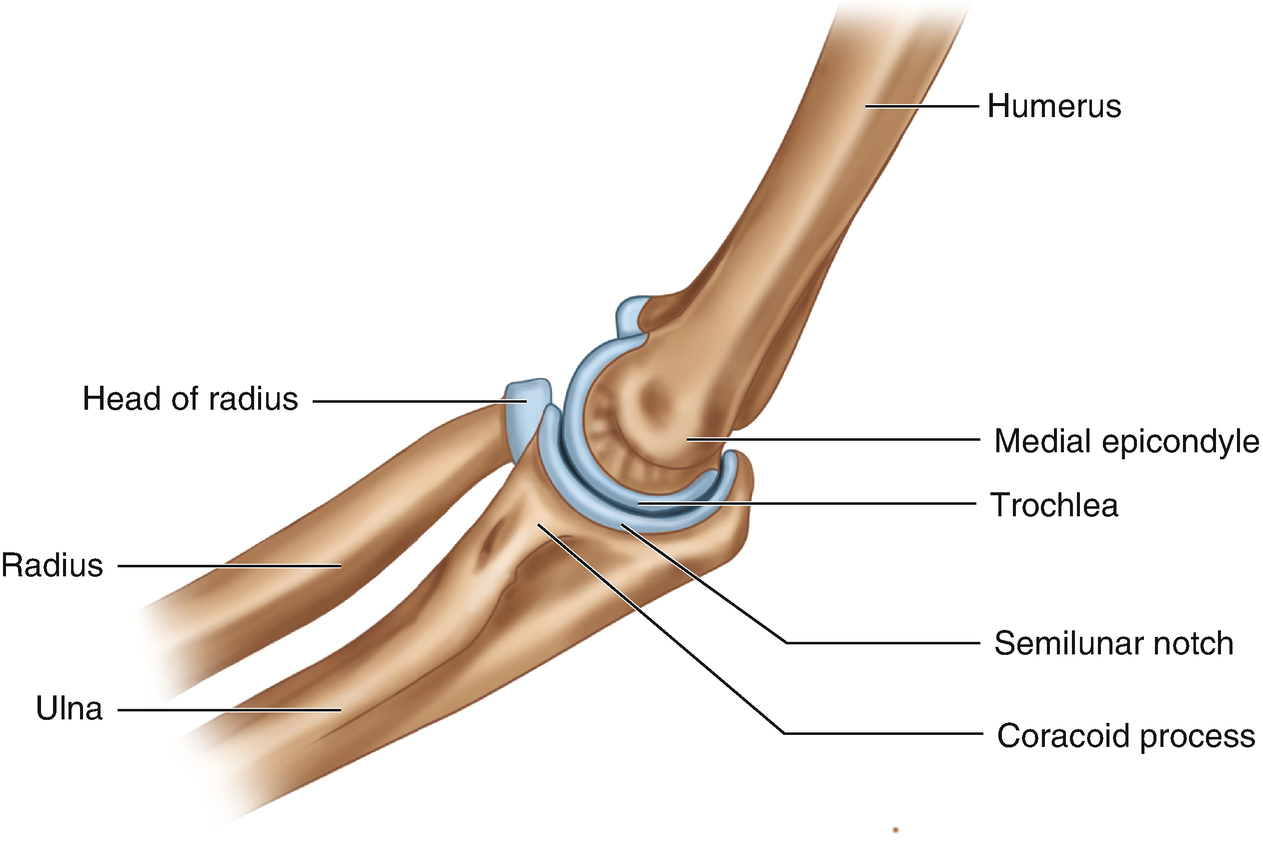

33.

You are doing tricep dips during practice. What joint connecting your ulna and radius to your humerus. allows for this motion?

Number 6 labels....

Question 29

29.

Number 7 labels....